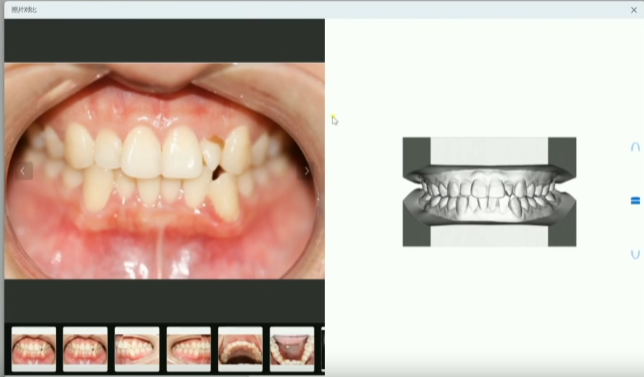

2、可视化排牙方案:提供模拟正畸的3D模型查看和对比功能,让患者能直观看到自己牙齿的3D形态和变化。